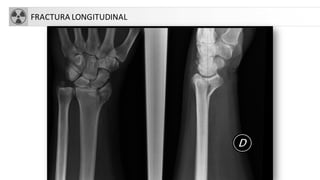

D. Longitudinal

FRACTURA LONGITUDINAL